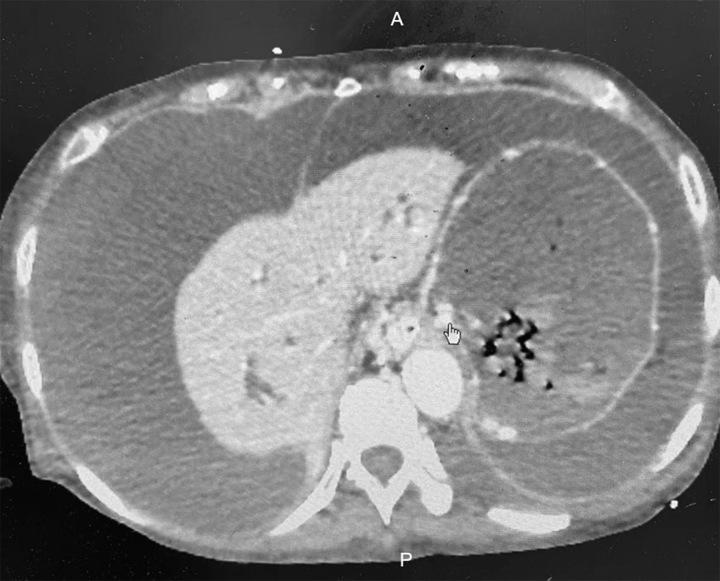

An 80-year-old female pancreatic cancer patient was admitted to our hospital on 22 January 2022 due to a massive gastrointestinal hemorrhage with shock after receiving radio-chemotherapy. Abdominal enhanced computerized tomography showed that the patient presented with pancreatic cancer-causing sinistral portal hypertension with massive collateral circulation, intrahepatic bile duct dilation, and the formation of massive ascites. Subsequent portography interventional procedure revealed the esophageal and gastric varix. Then, the varicose vein was embolized, and the stent was implanted at the lumen of the superior mesenteric vein accessing the portal vein. The patient recovered from pancreatic cancer-causing sinistral portal hypertension, and a normal direction of blood flow was observed in the superior mesenteric vein with a decreasing amount of ascites. In addition, a transfusion was also carried out, and the massive gastrointestinal hemorrhage was alleviated.

一名80岁女性胰腺癌患者于2022年1月22日因接受放化疗后出现大量胃肠道出血并休克而入住我院。腹部增强计算机断层扫描显示,该患者患有胰腺癌导致的左侧门静脉高压,伴有大量侧支循环、肝内胆管扩张和大量腹水形成。随后的门静脉造影介入手术显示食管和胃静脉曲张。然后,对曲张静脉进行栓塞,并在肠系膜上静脉进入门静脉的管腔内植入支架。患者从胰腺癌所致的左侧门静脉高压中康复,肠系膜上静脉血流方向正常,腹水减少。此外,还进行了输血,大量胃肠道出血得到缓解。